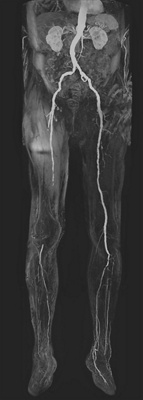

MRA-Gefässverschluss-rechter-OS

Verschliessen die Ablagerungen eine oder mehrere Arterien vollständig, droht das Bein unterhalb dieser Stelle abzusterben und muss amputiert werden.

Diese können mittels weiterer Untersuchungen (spezieller Gefäss-Ultraschall - Duplexsonografie) die betroffenen Stellen genauer lokalisieren und mit Ihnen die Behandlungsmöglichkeiten besprechen. Kommt eine invasive Behandlung in Betracht oder ist aufgrund einer schweren Durchblutungsstörung dringend notwendig, wird davor häufig eine umfassende Darstellung des Gefässsystems benötigt. Diese ist mittels Computer- oder Kernspintomographie relativ einfach ambulant und mit grosser Detailgenauigkeit bis in die Peripherie möglich.